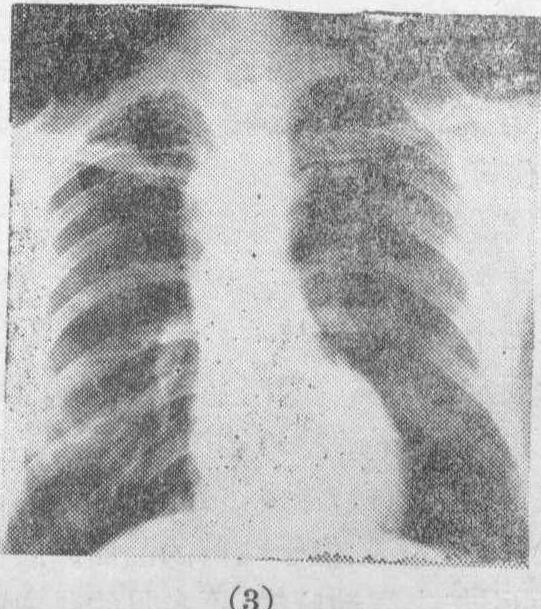

右位主动脉弓合并左位动脉韧带 此种病人,其主动脉弓位置与正常相反,乃因胚胎期左第四弓动脉形成左锁骨下动脉的近段,而右第四弓形成主动脉弓。后者经气管及食管的右侧上升,而下降常位于左侧,因而气管与食管乃位于其左前方,而不位于正常左位主动脉弓的右后方。动脉韧带常绕过气管与食管的左后方以连接主动脉及肺动脉,因而构成压迫该二管道的血管环,可引起明显的呼吸困难和吞咽障碍。(图3(1)(2))X线检查可发现主动脉弓位于右侧,吞钡摄片可发现食管受压征(图3(3))。食管镜检查可见主动脉弓水平食管有外压性狭窄。

图3 右位主动脉弓和左位动脉韧带(或导管)构成血管环,包绕气管和食管。

(1)从前面看。

(2)从后面看。

(3) X线检查所见,示主动脉弓位于右侧,并示含钡之食管受压征。